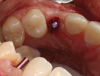

(11.) Conformation of the position and angulation of the initial osteotomy preparation of a patient who presented for replacement of the maxillary left canine.

Figure 11

(12.) Placement of an appropriately sized implant into the osteotomy.

Figure 12

(13.) The appropriateness of the apical depth of the implant head was confirmed.

Figure 13